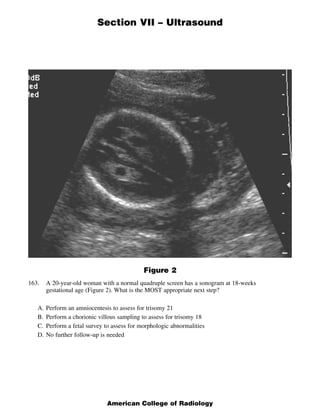

- Echogenic intracardiac focus is most commonly seen as a normal variant on prenatal ultrasound but should prompt careful examination for other abnormalities. - While it represents a normal variant, echogenic intracardiac focus has been associated with trisomy 13 and 21 but not trisomy 18. - The majority (90%) of echogenic intracardiac foci are located in the left ventricle, not the right ventricle as stated in one response option.